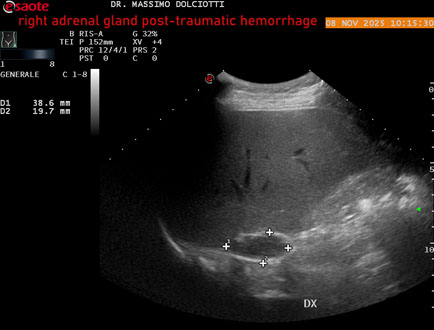

Data inserimento: 10/11/2025

Ecografia del: 08/11/2025

Strumento: Esaote MyLab Eight

Sonda: Convex Multifrequenza 1-8 MHz

Età Paziente: M 49 anni

Motivazione dell'esame: follow up per emorragia al surrene destro post-traumatica (incidente stradale).

Commento all'esame: le immagini ed il video documentano in sede surrenalica destra, formazione ipo-anecogena, a margini definiti, ovalare, delle dimensioni di 38,6 x 19,7 mm, da ricondurre ad emorragia post-traumatica.

Conclusioni: emorragia post-traumatica al surrene destro (post-traumatic hemorrhage to the right adrenal gland).

Presentazione: Dr. Massimo Dolciotti - Ancona

Elaborazione digitale: Andrea Dini - Ancona